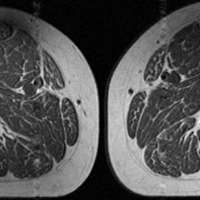

Ultraprocessed foods are turning human thighs into well-marbled steaks